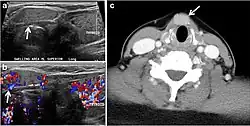

Fig. 17. Ectopic thyroid on the left parotid gland with a palpable left parotid mass in a 69-year-old male patient. a, b Axial and coronal enhanced neck CT scan demonstrates well-defined homogeneous enhancing mass (white arrows) within the left parotid gland with preserved surrounding fat planes. It also shows a normal thyroid in normal position in the lower neck. c Image taken 20 minutes after 5 mCi injected Tc99m-Pertechnetate shows normal thyroid uptake of tracer and physiological uptake in the salivary glands (short black arrow). There is a distinct focus of abnormal tracer accumulation in the left parotid/submandibular region. Patient was given lemon juice with evident normal washout from the salivary glands and relative retention by this abnormal focus (long black arrow).[1] -

Fig. 18. Lingular thyroid in a 33-year-old male who presented with oropharyngeal bleeding. an Axial enhanced neck CT scan at the level of mandible demonstrates a 3 × 3 × 3.4 cm round, partly well-delineated, heterogeneously enhancing lesion (white arrow). It is predominantly on the left side of the oropharynx and to some extent at the mid part of the base of the tongue. The thyroid gland was normal (not shown). b Image of the anterior face and neck taken 20 minutes after Tc99m-Pertechnetate injection shows absent thyroid radiotracer uptake in normal thyroid anatomical location (black short arrows). There is an area of increased uptake (long black arrows) corresponding to the posterior tongue mass identified on CT scan.[1]

Fig. 19. Long-standing infected thyroglossal duct cyst in a 29-year-old male patient. a Transverse greyscale ultrasound at midline, just above the level of the thyroid gland, shows an oval cystic lesion with internal echoes (white arrows) and posterior enhancement (arrowheads). b Transverse colour Doppler ultrasound shows surrounding peripheral flow (white arrow). c Axial enhanced neck CT scan at the level of the thyroid cartilage demonstrates a slightly off-midline, well-defined, homogeneous cystic lesion embedded in the left strap muscle with peripheral enhancement (white arrow). It shows no calcification or internal enhancement. Thyroid gland was normal (not shown).[1] -

Fig. 20. Recurrent/residual thyroglossal duct cyst in a 39-year-old male patient. The first resection of thyroglossal duct cyst showed histopathology evidence of Hurthle cell type thyroid cancer. However, the second resection showed signs of chronic inflammation, with no malignant cells. a, b Enhanced axial and sagittal neck CT scans demonstrate a unilocular cystic lesion arising from the tongue base and extending through the partially resected hyoid bone. This cystic lesion has a peripheral enhancing wall, which becomes more thick over its inferior aspect associated with surrounding fat stranding at the surgical site (white arrow). There are no internal septations, nodules or masses, or calcifications. c Transverse view of power Doppler ultrasound at the submental area demonstrates cystic lesion and internal debris with no detected internal vascularity.[1] -

Fig. 21. Papillary thyroid carcinoma arising from a thyroglossal duct cyst in a 28-year-old male. an Axial enhanced CT scan shows a large complex cystic lesion (white arrows) adherent to the anterior aspect of the hyoid bone. It has an enhancing mural solid nodules and calcifications (black arrows). There is no cervical lymphadenopathy. b Axial short tau inversion recovery (STIR) MRI image near the same level shows complex lesion of high signal intensity (long white arrows) with solid mural nodules (short white arrow). c Axial fat saturated T1 MRI image post contrast administration shows the complex cystic lesion with thick enhancing wall (long white arrows) and enhancing mural nodules (short white arrows).[1]